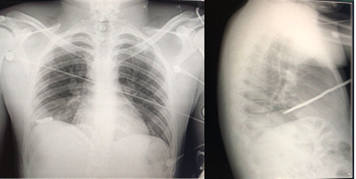

Chest examination revealed the presence of a carcinoma on the anterior aspect of the right hemithorax, mediclavicular line at the level of the 4th intercostal space (Figure 1). An extended FAST was performed, confirming the presence of a right pneumothorax. There was no evidence of free abdominal fluid or cardiopericardial occupation. The radiological pair performed in the emergency room shows an anteroposterior trajectory, from top to bottom with an angle of 30 degrees. The stabbing weapon, 25 cm long, is limited to the right hemithorax and does not appear to contact the right hemidiaphragm (Figure 2).

Figure 2 Radiological pair. Foreign body is evidenced giving an approximation of its trajectory.